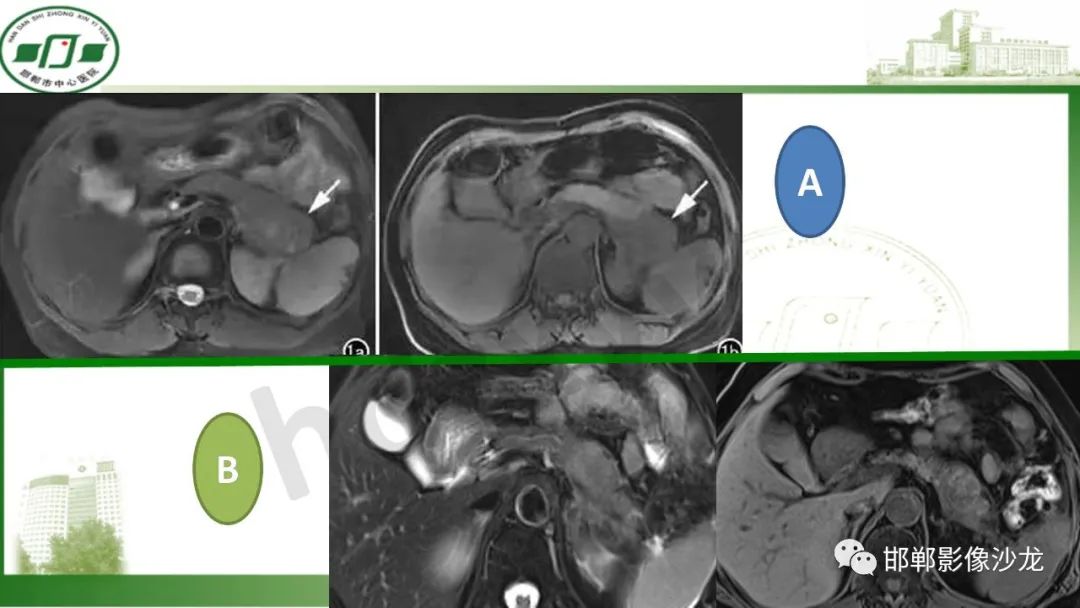

肿块性胰腺炎与胰腺癌的临床、实验室检查、影像学表现有时候很难鉴别,但两者的临床处理、预后又有很大的不同,因此我们平时工作中需要注意两者之间的区别,谨慎诊断,力争为患者及临床带来更大的帮助。